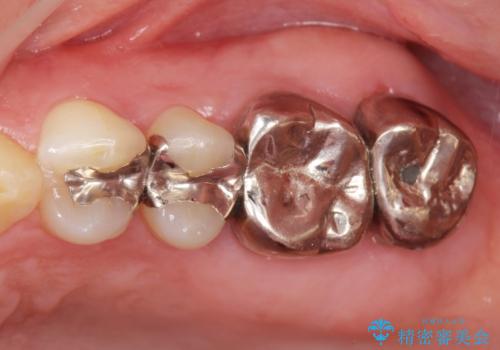

- 銀歯をやりかえたいが他院で抜歯と言われセカンドオピニオンで来院。適合の悪い被せ物が入っており、まずは古い材料、虫歯をとり保存可能か確かめる必要があり、拡大鏡下で全て取り除いたら歯質が歯茎の中まで虫歯がありました。このまま無理やり型取りをして被せ物を作っても不適合な被せ物が入る可能性が高いため歯茎を切り取る手術(ディスタルウェッジ)を行いました。そして再根管治療を行いゴールドの被せ物で治療を行いました。